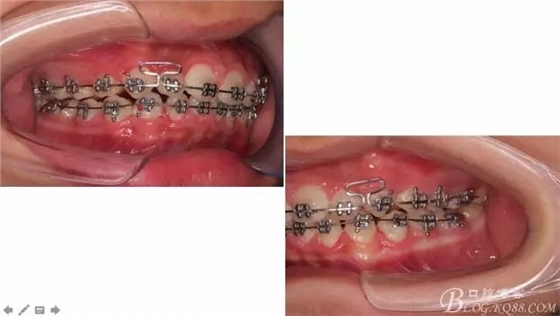

看看口內(nèi)照吧!真象“大暴牙”v假象“大暴牙”

三度深覆合,三度深覆蓋,尖牙,磨牙均二類關(guān)系!